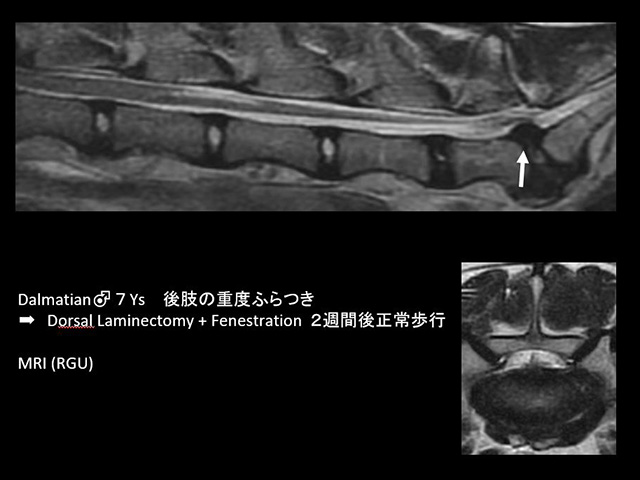

症状は、軽度のふらつきから後肢(頚部椎間板ヘルニアでは前肢または四肢)の麻痺まで様々であり、疼痛症状だけの場合もあります。

椎間板ヘルニアの症例に対しての治療は、これまで、問診・初期検査(神経学的検査、血液検査、X線検査など)・CT検査・手術などの一連の診断治療におよそ2時間で対応し、多くの動物が歩行可能な状態にまでに短期間で回復しています。